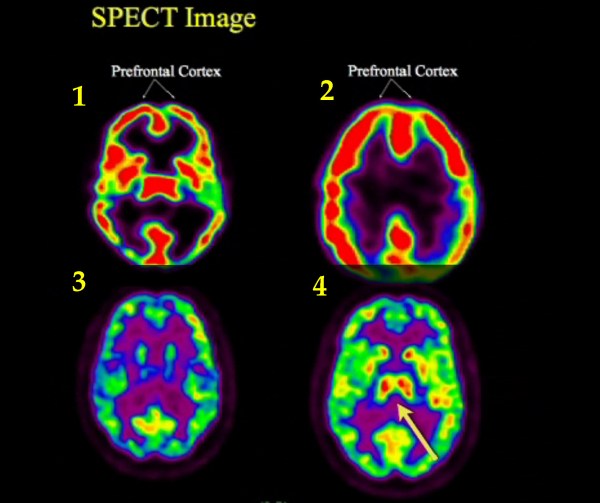

Simulación de un ‘SPECT‘ del cerebro de Becks en las cuatro fases de su agonía: 1.- Escaner en estado normal. Flujo distribuido. 2.- Lóbulos frontales con mayor flujo. Se pone atención en los músculos. Apenas hay actividad en el centro o de ‘recuerdos’. 3.- Flujo desaparece. Casi no hay actividad. 4.- La parte central o de recuerdos se ilumina de nuevo, al pensar en su familia.